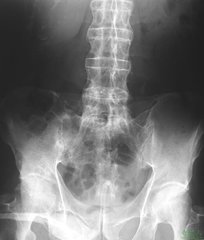

怎么才能预防强直性脊柱炎?大家对强直性脊柱炎有所了解,应该不会感到陌生。而今,强直性脊柱炎的发病率越来越高,作为正常人的我们,应该如何预防强直性脊柱炎呢?

如何预防强直性脊柱炎